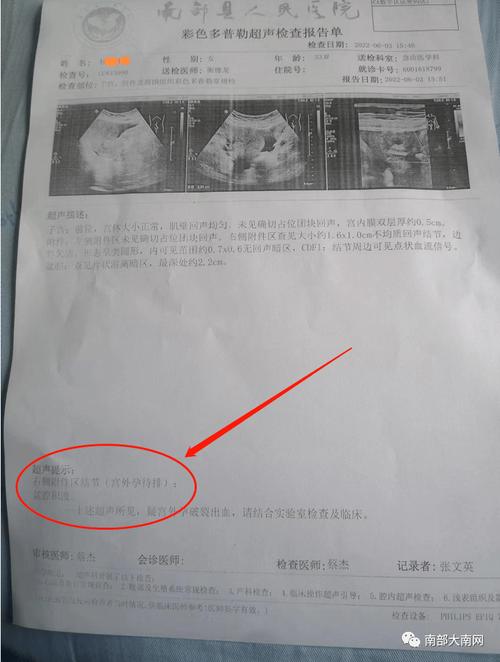

宫外孕当急性阑尾炎手术南部县人民医院最新回复

图片尺寸714x946